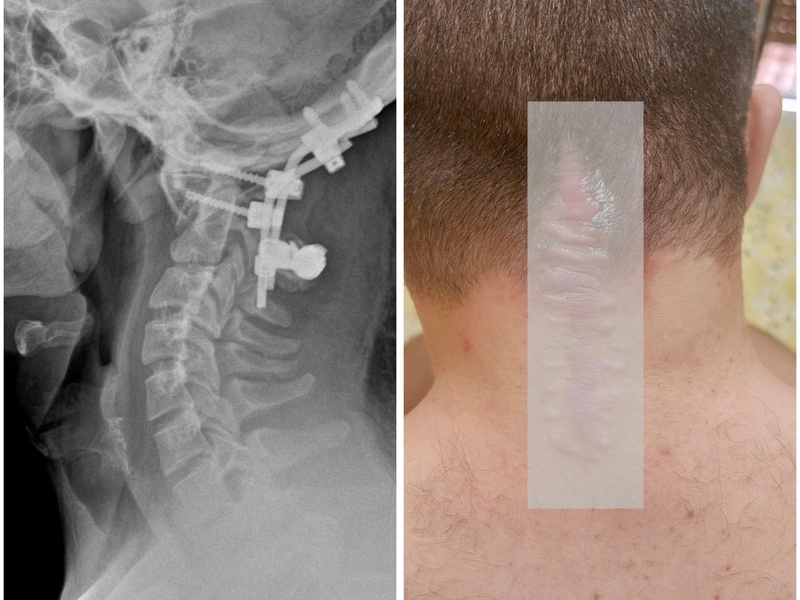

La difficoltà di deambulazione del ragazzo è stata causata da un intervento di stabilizzazione occipito-cervicale, certificata e documentata da RX e referti medici.